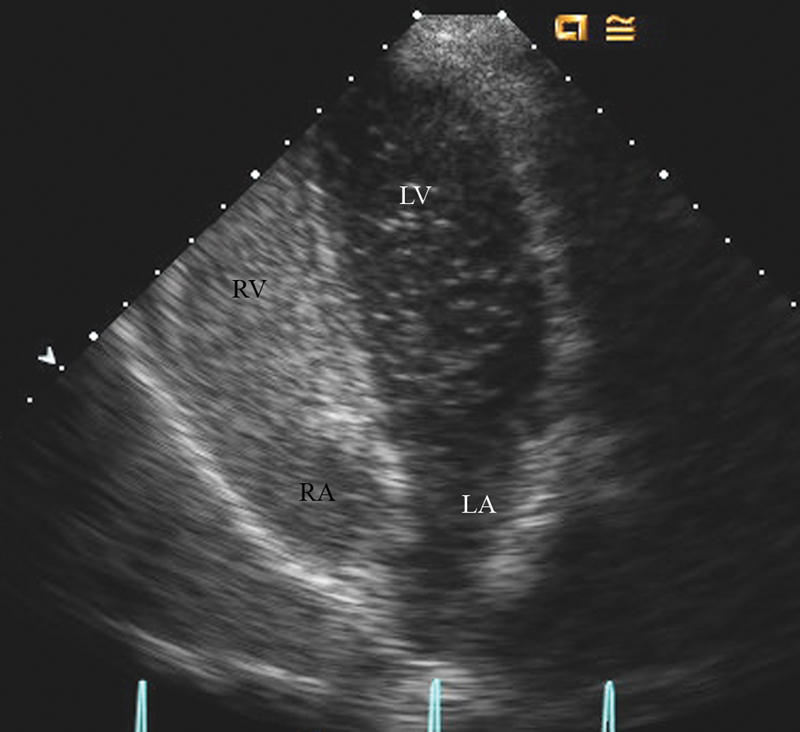

فحوصات تشخيصية لبعض امراض القلب والشرايين التاجية